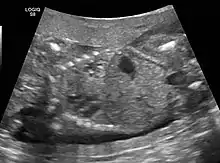

CPAMs are often identified during routine prenatal ultrasonography. Identifying characteristics on the sonogram include: an echogenic (bright) mass appearing in the chest of the fetus, displacement of the heart from its normal position, a flat or everted (pushed downward) diaphragm, or the absence of visible lung tissue.

The earliest point at which a CPAM can be detected is by prenatal ultrasound. The classic description is of an echogenic lung mass that gradually disappears over subsequent ultrasounds. The disappearance is due to the malformation becoming filled with fluid over the course of the gestation, allowing the ultrasound waves to penetrate it more easily and rendering it invisible on sonographic imaging. When a CPAM is rapidly growing, either solid or with a dominant cyst, they have a higher incidence of developing venous outflow obstruction, cardiac failure and ultimately hydrops fetalis. If hydrops is not present, the fetus has a 95% chance of survival. When hydrops is present, risk of fetal demise is much greater without in utero surgery to correct the pathophysiology. The greatest period of growth is during the end of the second trimester, between 20–26 weeks.